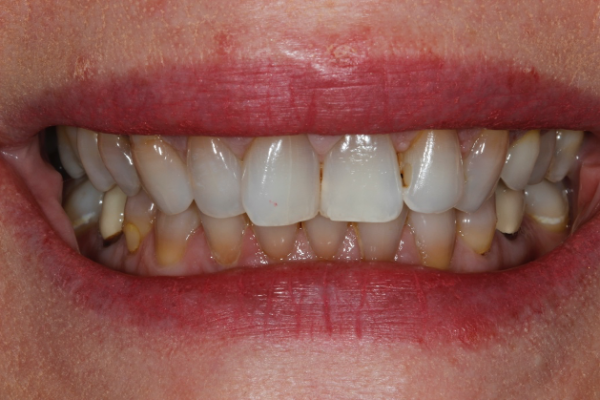

In the case shown, (Figure 1a) the patient wanted her teeth to be completed prior to her wedding in 14 weeks from the time she presented. She also requested a material with the longest performing clinical lifespan.

If all of these considerations are taken into account with this case, we can see that the upper right central incisor would be subject to significant tooth reduction (Figures 1b and 1c) and the risk of iatrogenic pulpal death would be increased. Even with immediate dentine sealing and other protective practices adopted.

So, prior to a hygiene work up, the patient was then assessed from an orthodontic perspective for short-term pre-restorative orthodontics. This was to improve tooth position (Figures 2 a,b and c) and allow for a less destructive tooth preparation.